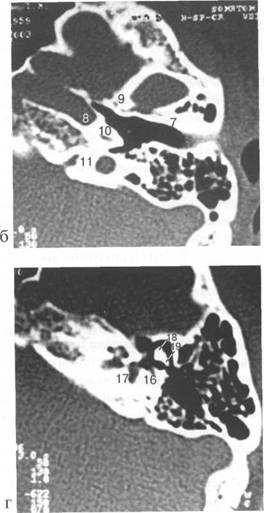

(mesotympanum), (epitympanum) (hypotympanum).

(adidus ad antrum), (attic) (m. stapedius).

(promontorium), (m. tensor tympani). (fenestra ovalis), (fenestra rotundum),

recessus epitympanicum, (tegmen tympani)

(antrum mastoideum), adidus ad antrum

«bone» «edge»

m. tensor tympani,

tegmen tympani,